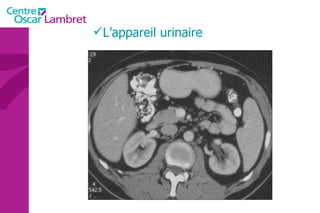

L’appareil urinaire L’appareil urinaire se compose des reins, des uretères et de la vessie. Les reins  sont rétro-péritonéaux : de part et d’autre du rachis entre T12 et L3. Fixés sous les côtes, ils sont en liaison avec l’artère rénale . Le rein possède une fonction secrétoire puis excrétoire à partir du pyelon, origine de l’uretère.

L’appareil urinaire

L’appareil urinaire Les uretères  se dirigent vers le bas, en avant et en dedans pour rejoindre la partie postéro supérieure de la vessie. On distingue 3 parties : L’uretère lombaire (12 cm) L’uretère iliaque (3 cm) L’uretère pelvienne (12 cm)

La vessie  : Elle recueille l’urine qui lui parvient par les uretères. L’urine est évacuée par l’urètre lors de la miction. L’appareil urinaire

Les surrénales  sont 2 glandes endocrines triangulaires situées au dessus des reins. Elles sont principalement responsables de la gestion des situations de stress via la synthèse de corticostéroïdes et de cathécolamines, entre autres le cortisol et l‘adrénaline.  Intérêt d’un balisage digestif pour l’étude de ces glandes L’appareil urinaire